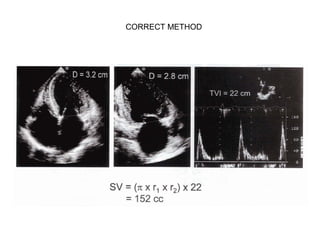

CORRECT METHOD

STROKE VOLUME ATMITRAL ANNULUS